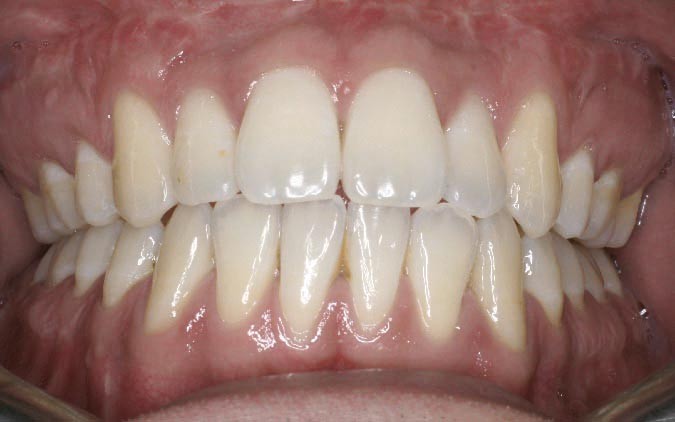

Les résultats esthétiques et occlusaux satisfont amplement le patient qui revient pour un contrôle à long terme 10 ans après l’intervention montrant la stabilité des résultats.